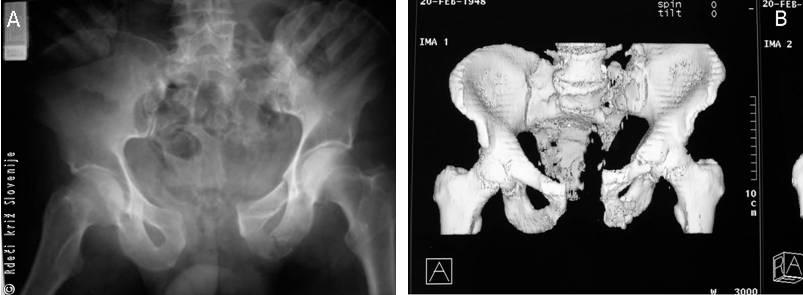

Slika 7

A – RTG.

B – 3D CT visokoenergijske, povsem nestabilne poškodbe medenice. Sodobne slikovne diagnostične naprave omogočajo hitro in natančno analizo poškodb ter pravilno načrtovanje in izvedbo dokončnega zdravljenja.